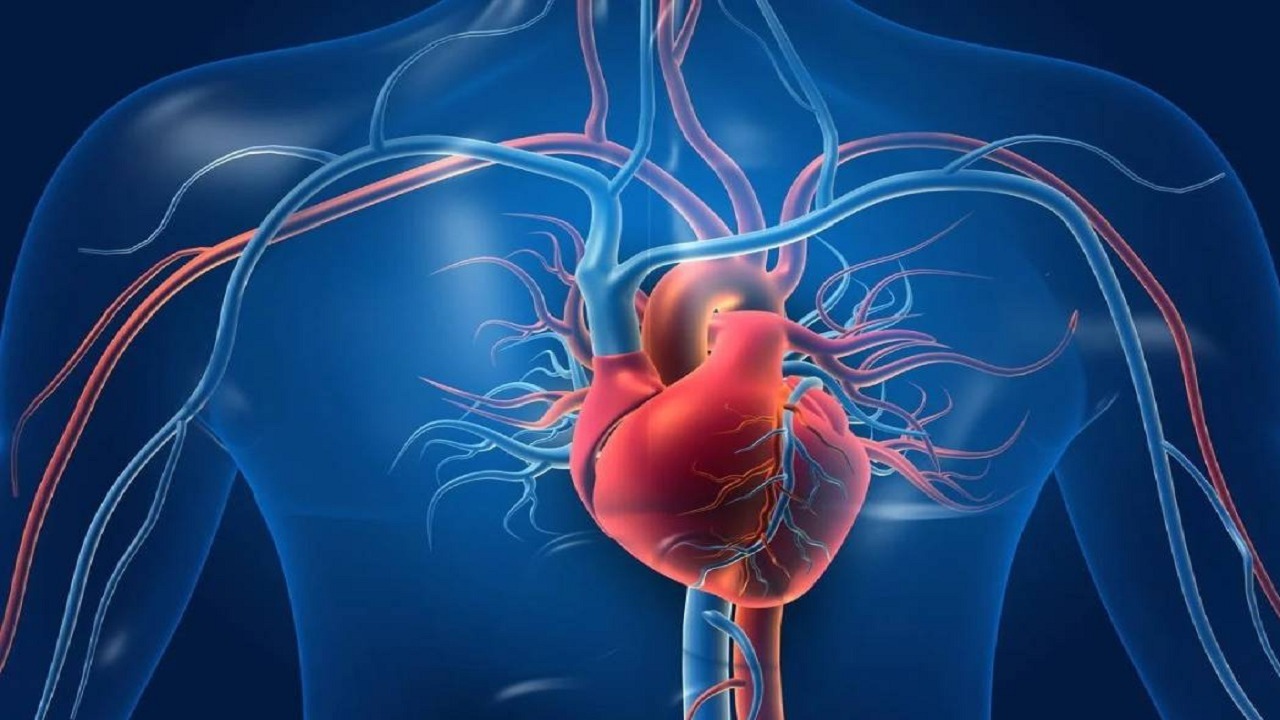

القلب